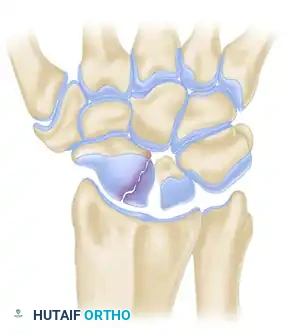

Surgical Anatomy and Fracture Classification

Understanding the three-dimensional orientation of the scaphoid is paramount for successful percutaneous fixation. The scaphoid lies at an oblique angle—approximately 45 degrees to both the sagittal and coronal planes of the wrist.

Fractures are generally classified by their anatomic location: distal pole, waist (middle third), and proximal pole. Waist fractures are the most common, accounting for 70-80% of all scaphoid fractures. Proximal pole fractures have the highest rate of nonunion and osteonecrosis due to the retrograde blood supply.

Clinical Pearl: The central axis of the scaphoid is the biomechanically optimal position for screw placement. A screw placed down the central third of the scaphoid provides maximum stiffness, highest load to failure, and optimal compression across the fracture site.